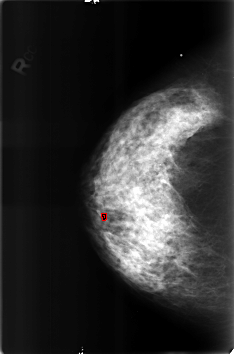

B_3175_1.RIGHT_CC

RIGHT_CC LINES 4592 PIXELS_PER_LINE 3040 BITS_PER_PIXEL 12 RESOLUTION 50 OVERLAY

FILE: B_3175_1.RIGHT_CC.OVERLAY

TOTAL_ABNORMALITIES 1

ABNORMALITY 1

LESION_TYPE CALCIFICATION TYPE LUCENT_CENTER DISTRIBUTION N/A

ASSESSMENT 2

SUBTLETY 3

PATHOLOGY BENIGN_WITHOUT_CALLBACK

TOTAL_OUTLINES 1

BOUNDARY